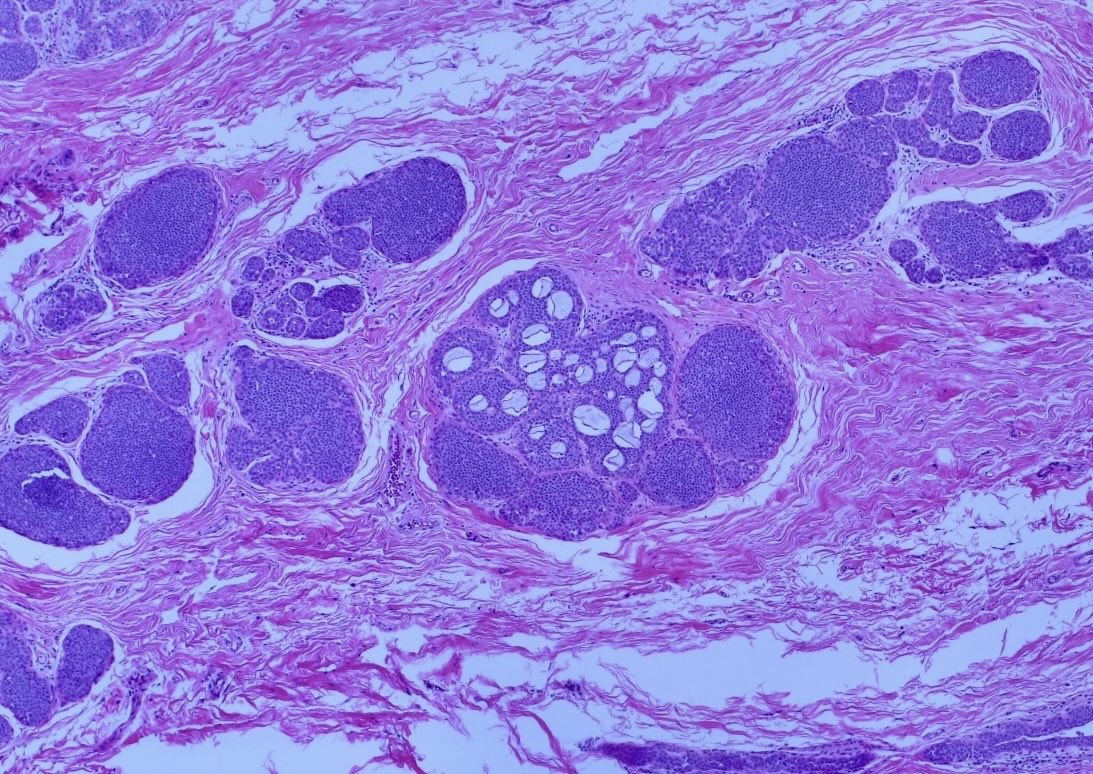

#Pathresidents #Surgpath #breastpath #pathology An incidental finding in a reduction mammoplasty in a 50 year old woman with no significant history. Read on for a poll and a quick discussion.

BrownPathology's tweet image. #Pathresidents #Surgpath #breastpath #pathology

An incidental finding in a reduction mammoplasty in a 50 year old woman with no significant history.

Read on for a poll and a quick discussion.